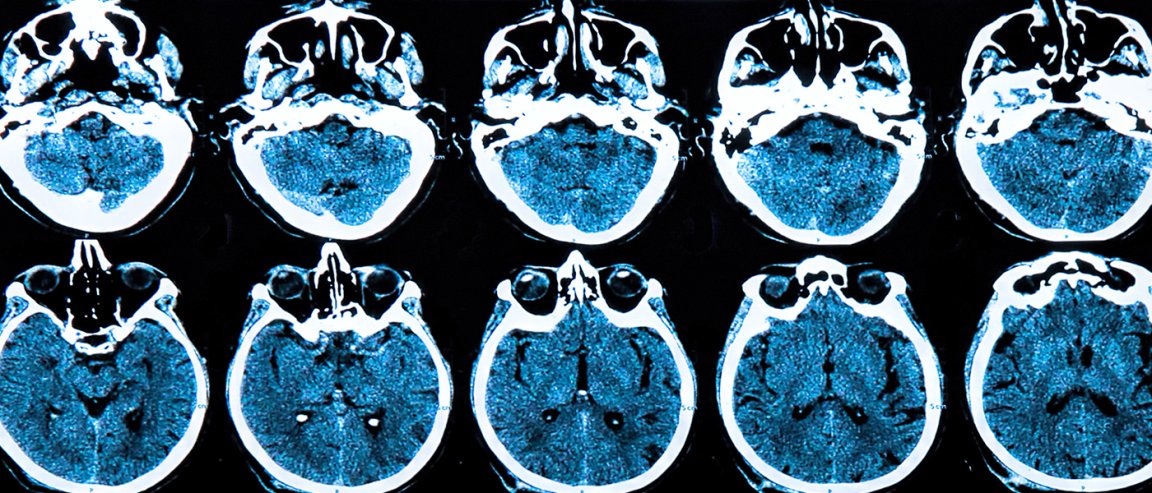

This medical revolution will be further bolstered by new and improved imaging techniques. A big part of the problem we still have with this disease is that we can’t actually see what is wrong. Every person who has PD has slightly different symptoms but we don’t really know why primarily because we can’t accurately see inside patient’s heads. Soon a new line of imaging techniques will be available that will give surgeons and researchers a much better understanding of what is going on inside the heads of each patient.